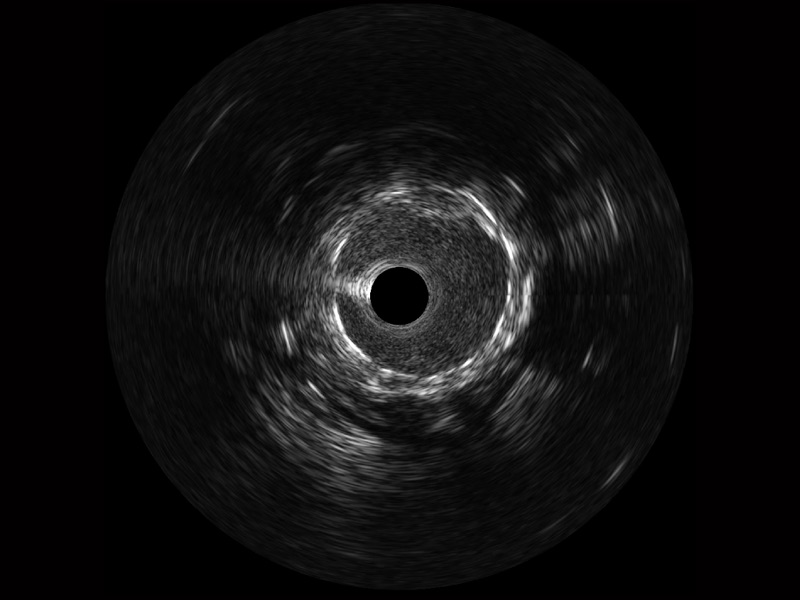

传统IVUS图像

对比传统IVUS导管成像,玖鼎集团宽频IVUS图像的近场支架梁显影更细腻,远场中膜外血管仍清晰可辨,兼顾远中近,兼顾分辨力与穿透深度